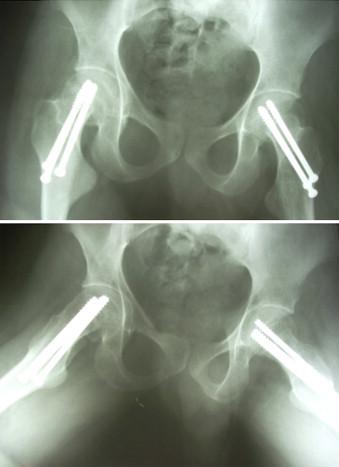

This report presents a case of bilateral femoral neck fractures that occurred during an epileptic attack in a 24-year-old male with mental retardation. His complaints had started after a grand mal epileptic attack 10 days earlier. Bilateral displaced femoral neck fractures (Garden type 4) were seen in lateral radiographs of both hips. The patient was operated on urgently, with closed reduction, three stainless steel cannulated screws, and internal fixation applied to both hips. At postoperative week 12, solid joining was achieved and active walking with complete loading was started.

本报告呈现了一例24岁智力发育迟缓男性在癫痫发作时发生双侧股骨颈骨折的病例。他的症状在10天前一次大发作癫痫后开始出现。双髋部侧位X线片显示双侧股骨颈骨折移位(Garden 4型)。患者接受了紧急手术,进行了闭合复位,在双髋部应用了3枚不锈钢空心螺钉并进行内固定。术后第12周,实现了牢固愈合,并开始完全负重的主动行走。